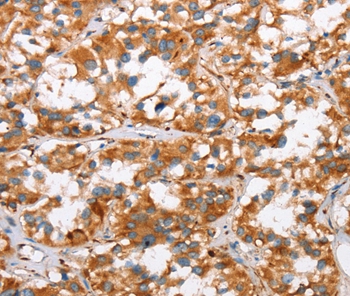

Immunohistochemical analysis of paraffin-embedded Human thyroid cancer tissue using #37439 at dilution 1/30.